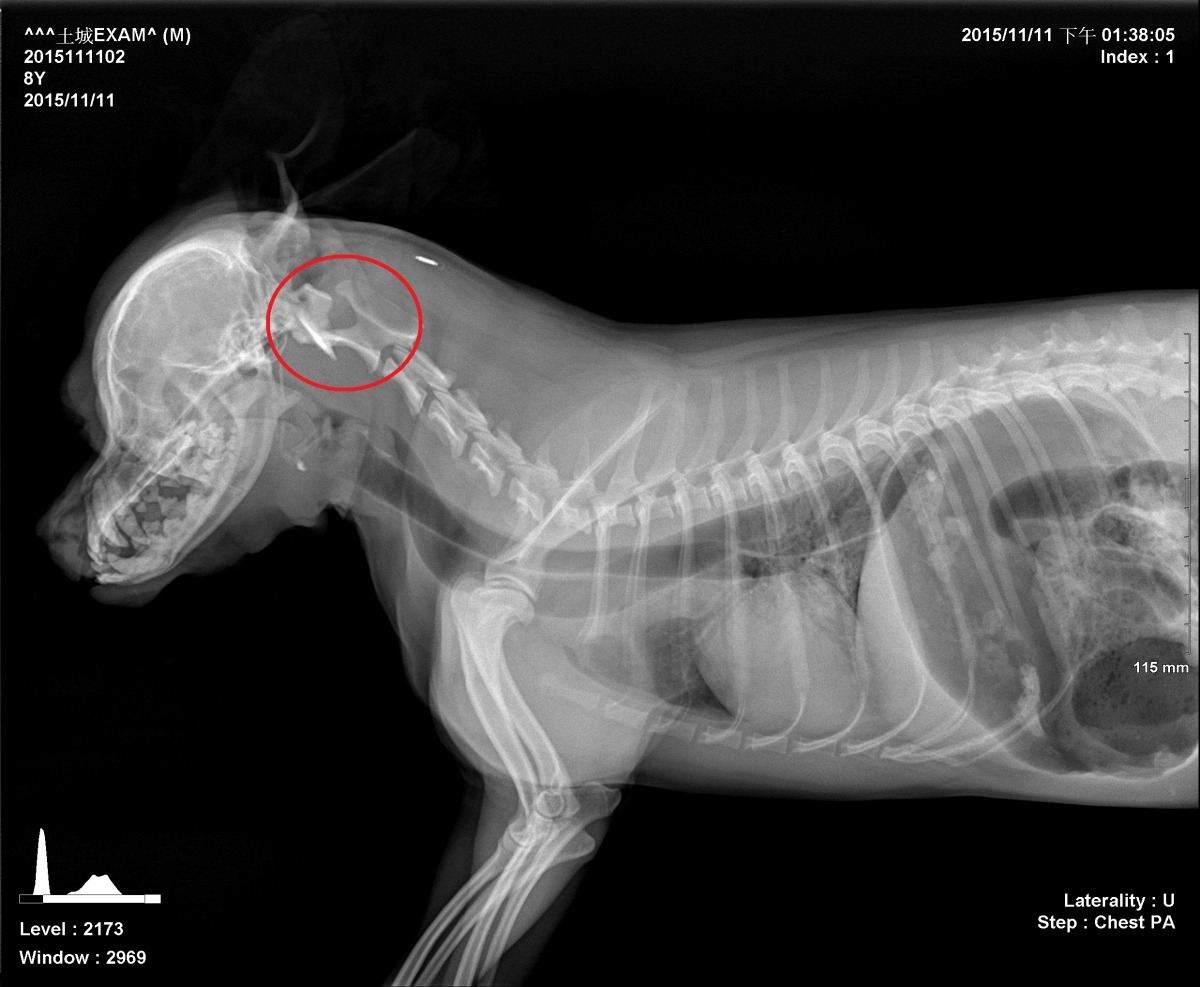

新北市土城學府店的「喜羊羊寵物生活館」,昨(10)日晚間驚傳一名美容師在替狗狗修毛時、粗暴對待狗狗導致死亡的事件。雖然今天一早喜羊羊寵物生活館總公司立即發出道歉聲明,但仍止不住民眾的抗議聲浪,紛紛在網路上留言請該名將狗虐死的林姓美容師「出來面對」!下午新北市動物保護處以X光檢視後,發現狗狗為頸椎脫位死亡。

新北市動物保護處處長陳淵泉表示,下午派員至土城分局了解案情後,以X光機檢驗龍龍屍體,發現死因是頸椎脫位。據了解龍龍在受不了林姓美容師粗暴對待而癱軟下來後,緊急送至鄰近大曜動物醫院施打強心針急救仍不治死亡。透過監視器影片確定美容師有傷害動物行為,因違反動物保護法第25條罰則,可判處一年以下有期徒刑或拘役,併科新臺幣10-100萬元之罰金,目前全案已移送至地檢署辦理。